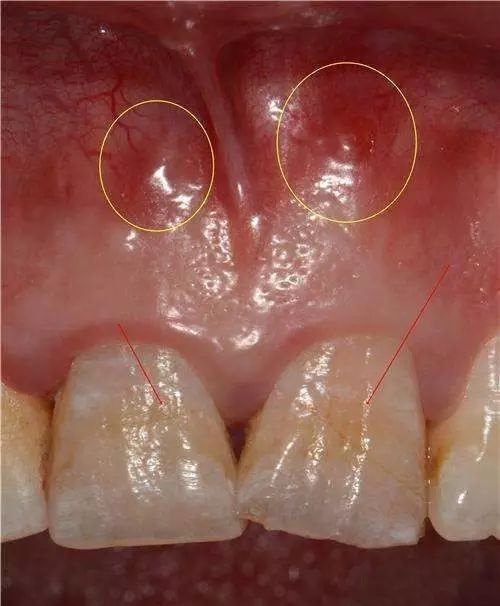

3)根管壁侧穿 手用扩大针作根管清理或扩大,较少出现侧穿现象,除非是用大号扩大针作强行扩大。采用机用扩大针或桩冠修复时进行钉道制备,如操作不慎较易侧穿。侧穿后如未发现或处置不当,日后可出现有窦道的慢性根尖周炎。